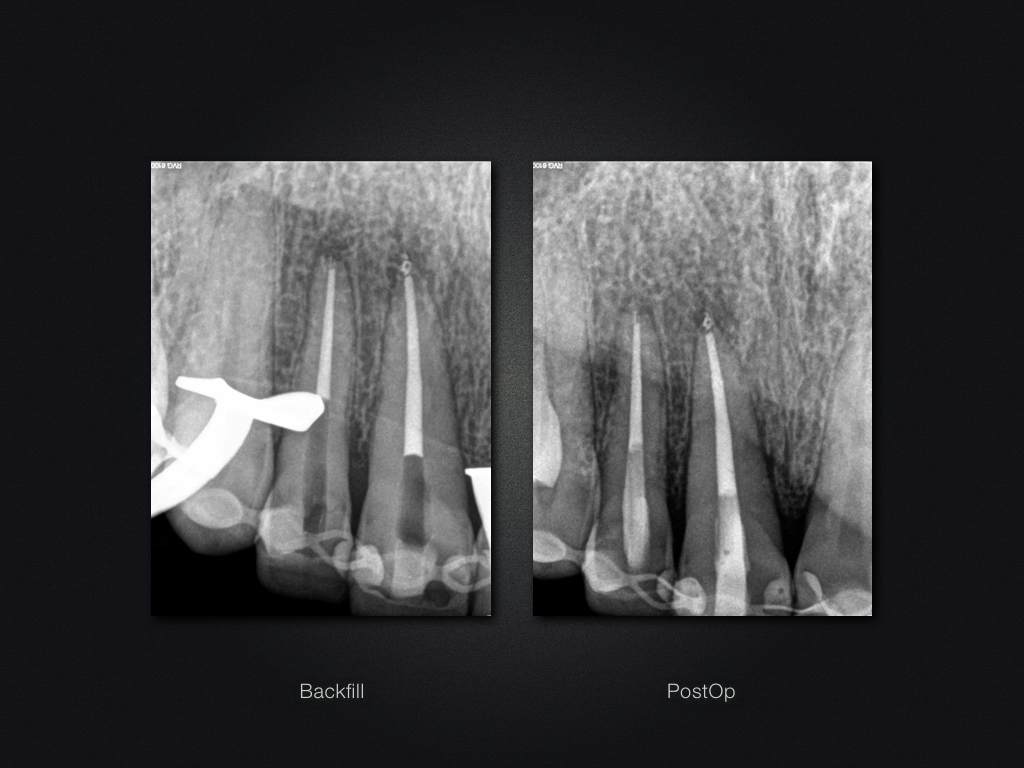

11 21 D.013

Recall nach Frontzahntrauma